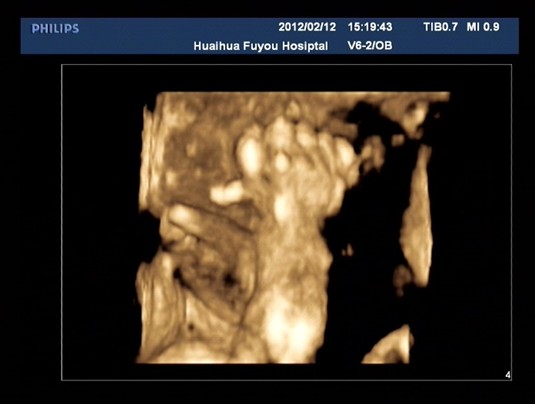

手、足畸形是孕婦們非常關(guān)注,檢查過程中經(jīng)常詢問的問題,也是來醫(yī)院做四維彩超檢查的目的之一。近日我院四維彩超就檢出一例多指畸形(見圖:為右手第一掌指關(guān)節(jié)處第六指畸形),是在孕27周胎兒體位相對(duì)較好的情況下偶然發(fā)現(xiàn)的。多指是最常見的手畸形,可以長在拇指側(cè),也可長在小指側(cè),可為一單純的軟組織皮贅,也可為一包含部分指骨額外手指。

產(chǎn)前超聲對(duì)手畸形的檢出與辨認(rèn)相對(duì)較困難,影響超聲對(duì)手畸形的觀察與辨認(rèn)的主要因素有胎兒體位的影響,胎手的運(yùn)動(dòng)、握拳或半握拳狀態(tài),羊水少等。四維超聲在顯示正?;虍惓5氖滞蟆⑹终?、手指主面很有幫助,對(duì)手的空間關(guān)系顯示更直觀,但要獲得清楚的胎手四維圖像較二維更困難,只有在經(jīng)驗(yàn)豐富醫(yī)師細(xì)心檢查和良好的羊水襯托下,四維彩超才能更清楚顯示出多余手指。因此四維彩超不是萬能的,特別是對(duì)于多指畸形而言,請(qǐng)準(zhǔn)媽媽們正確認(rèn)識(shí)四維彩超檢查。